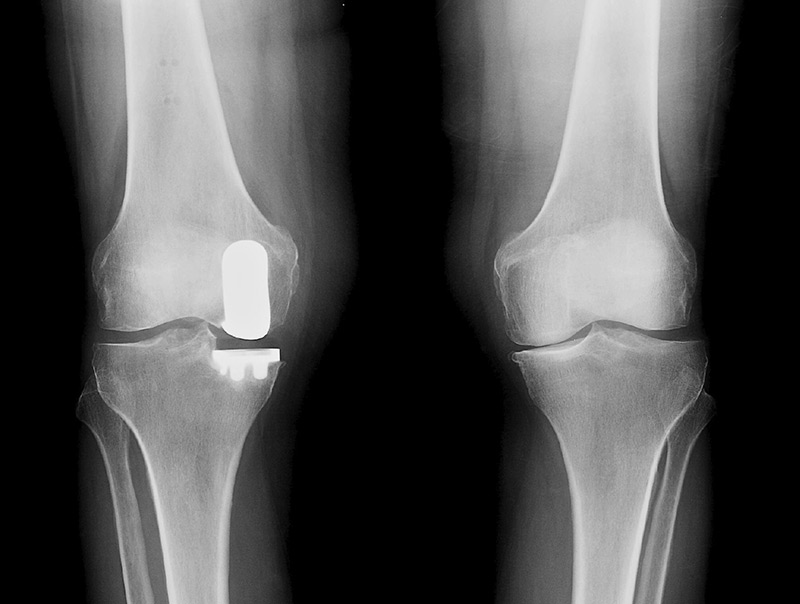

Απομονώνοντας το διαμέρισμα του γόνατος που έχει υποστεί βλάβη από την ΟΑ, ο χειρουργός μπορεί επιλεκτικά να αντικαταστήσει τις κατεστραμμένες αρθρικές επιφάνειες  ενώ παράλληλα διατηρεί ανέπαφα τα υγιή οστά και τους συνδέσμους που τον περιβάλλουν.

Η ρομποτική τεχνολογία MAKO παρέχει στον χειρουργό ένα εξατομικευμένο τρισδιάστατο (3D) μοντέλο για τον κάθε ασθενή έτσι ώστε ο χειρουργός να πραγματοποιήσει τον προ-εγχειρητικό σχεδιασμό της μερικής αντικατάστασης του γόνατος με μεγάλη ακρίβεια.

Κατά τη διάρκεια της χειρουργικής επέμβασης, ο χειρουργός καθοδηγεί το ρομποτικό βραχίονα MAKO βάσει του προεγχειρητικού σχεδιασμού. Αυτό επιτρέπει στον χειρουργό να αφαιρέσει μόνο το κατεστραμμένο οστό, διατηρώντας ανέπαφα τα υγιή οστά και τα μαλακά μόρια ενώ βοηθά τον χειρουργό να τοποθετήσει το εμφύτευμα με ακρίβεια βάση την ανατομία του ασθενούς.

Αυτό περιλαμβάνει αφενός την δημιουργία ενός στερεοτακτικού παραθύρου (απαραίτητο για την ακριβή αφαίρεση του παθολογικού οστού) αφετέρου την επιλογή του ιδανικού μεγέθους του εμφυτεύματος και την τοποθέτησή του με τέτοιο τρόπο ώστε να επιτευχθεί η επιθυμητή μετεγχειρητική κάλυψη των οστών και η σωστή ευθυγράμμιση του σκέλους.